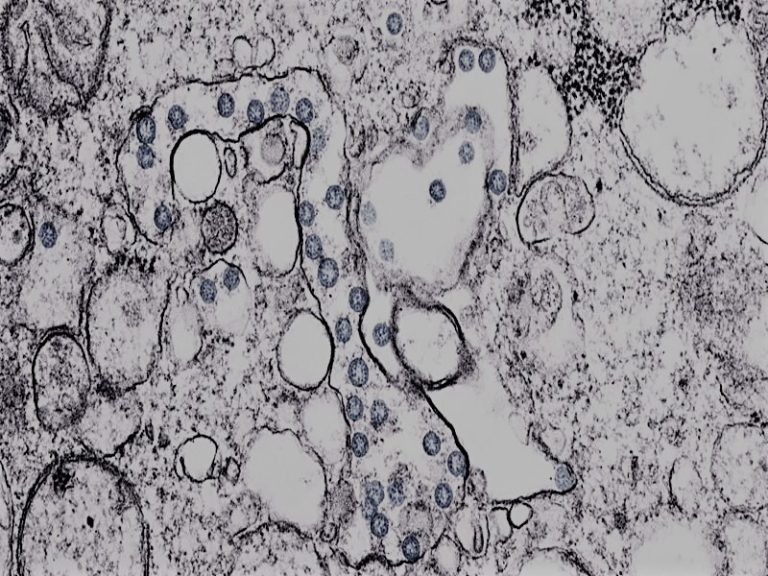

Viruses are also genetic innovators – and possibly the pioneers of using DNA as the genetic blueprint...